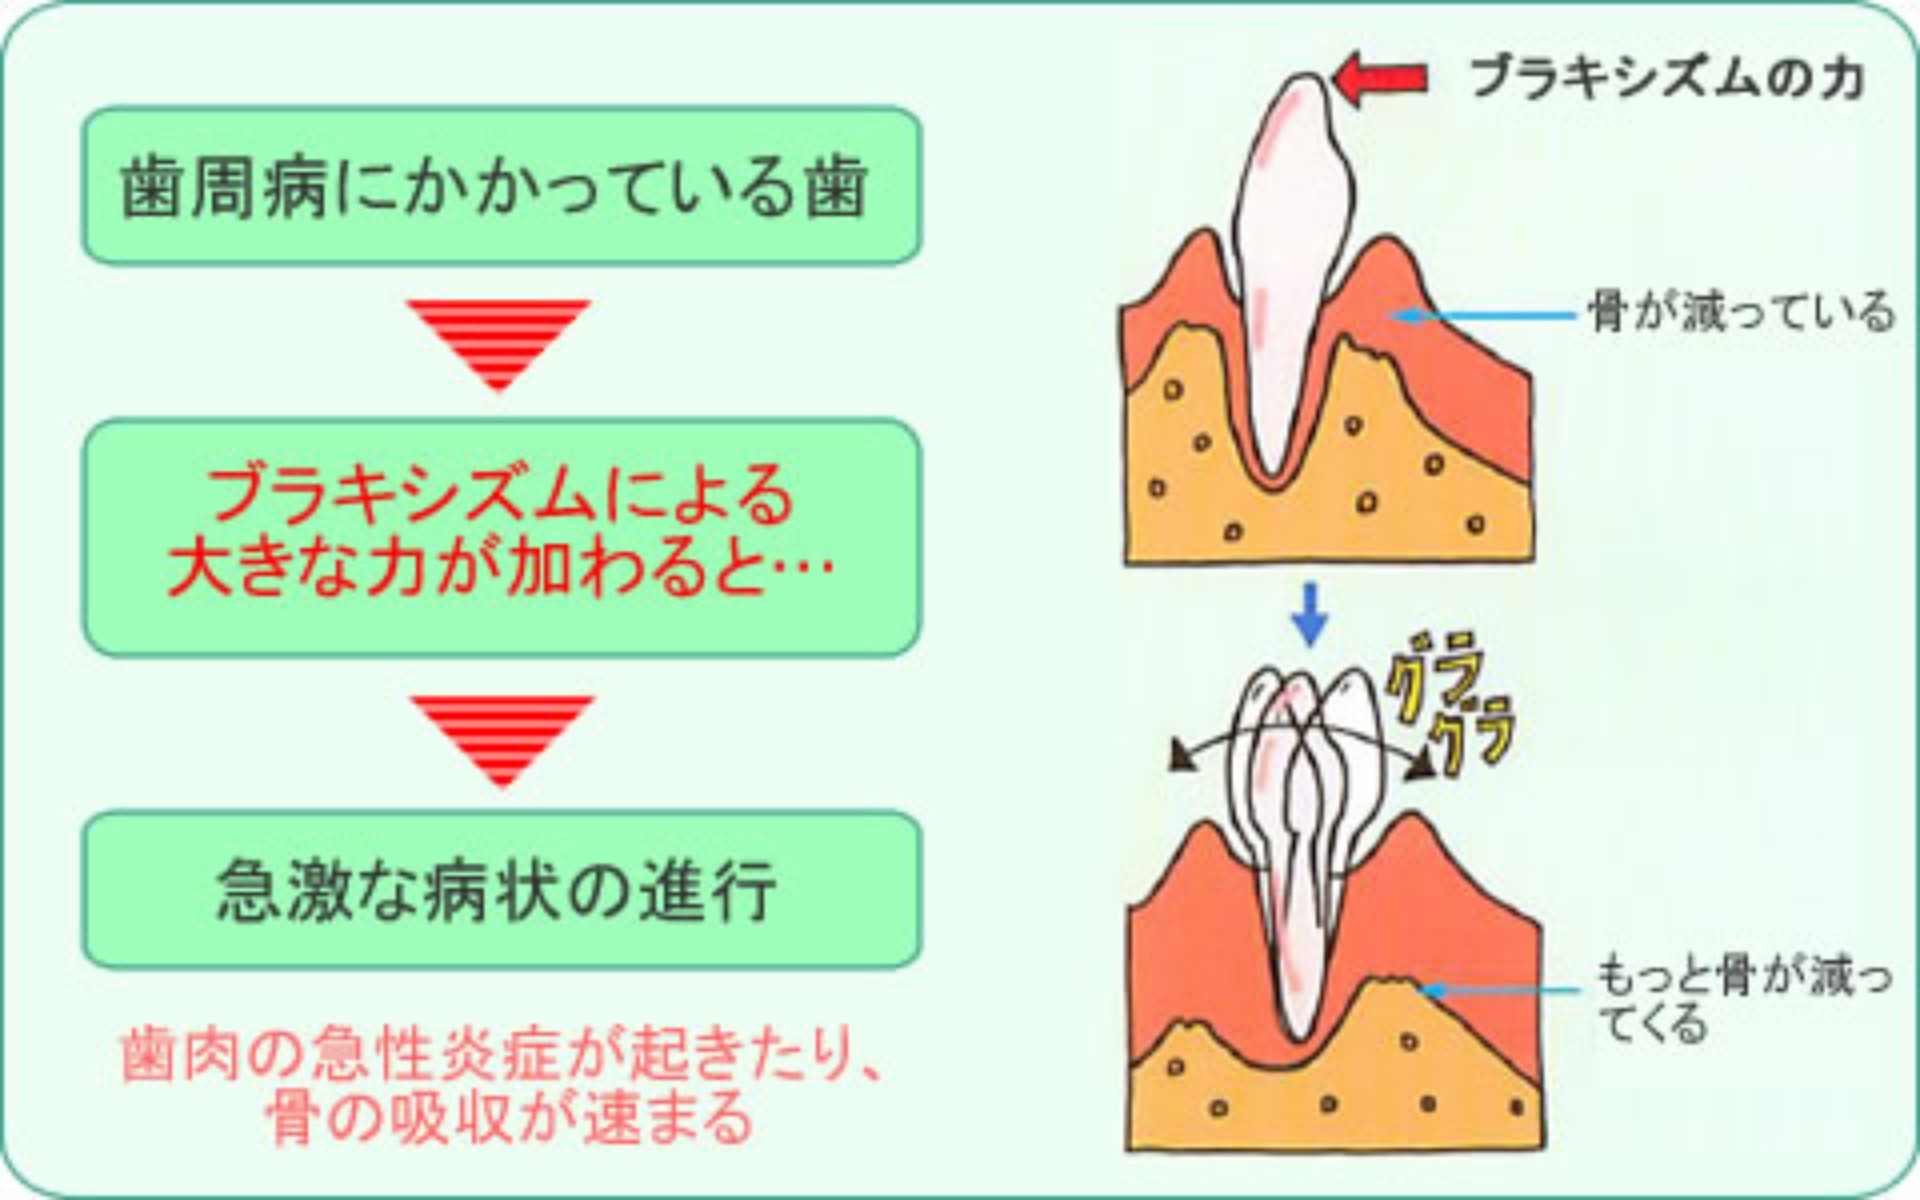

●歯肉・歯槽骨(歯を支える骨)への影響と弊害

歯周病にかかっている歯に、さらにブラキシズムによって大きな力が加わると、急速に歯肉や歯槽骨の状況が悪化することがあります。

歯周病との相乗作用

この状態を放ったままにしておくと、抜歯せざるをえなくなることもあります。